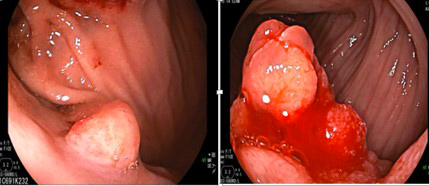

上消化道内镜检查可见十二指肠和胃体有多发息肉,最大者直径超过3cm。对这些息肉进行活检或切除后进行病理检查,结果提示是错构瘤性息肉(PJ息肉)和增生性息肉。

胃体(左)和十二指肠(右)多发息肉